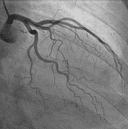

Coronarographie et imagerie invasive

Pr Jean-Guillaume Dillinger

CHU Lariboisière, AP-HP